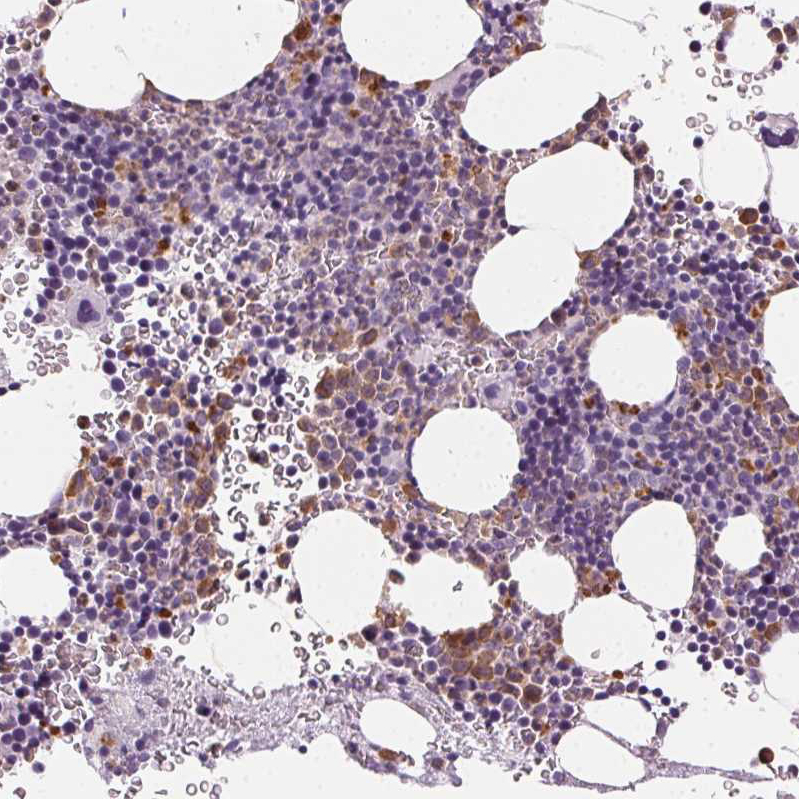

Immunohistochemistry analysis in human bone marrow and cerebral cortex tissues using HPA021147 antibody. Corresponding MPO RNA-seq data are presented for the same tissues.